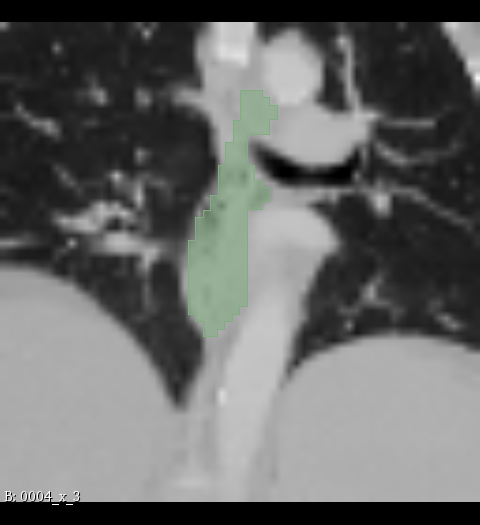

Figure 2: Illustration of the data from the TotalSegmentor data set [32] used in the experiments. The first row shows the axial, coronal and sagittal views passing the center of mass of the kidney in one of the data points. The second row shows the axial, coronal and sagittal views passing the center of mass of the aorta in one of the data points. The third row shows the axial, coronal and sagittal views passing the center of mass of the esophagus in one of the data points.

5.1 Data

The experiments are conducted with respect to the TotalSegmentor data set [32]. This data set contains 1204 CT images with 104 anatomical structures (27 organs, 59 bones, 10 muscles, 8 vessels). To illustrate the effect noise may have on organs with different shape, three different organs are chosen. This includes the right kidney which in general is pretty spherical, the aorta which is tubular and relatively thick and the esophagus which is tubular and relatively thin. For each of the organs, 400 cases is selected and split into 5 folds of 80 cases. Finally, the images are sub-sample to half resolution and patches of 643superscript64364^{3} voxels centered in each of the structures are extracted.